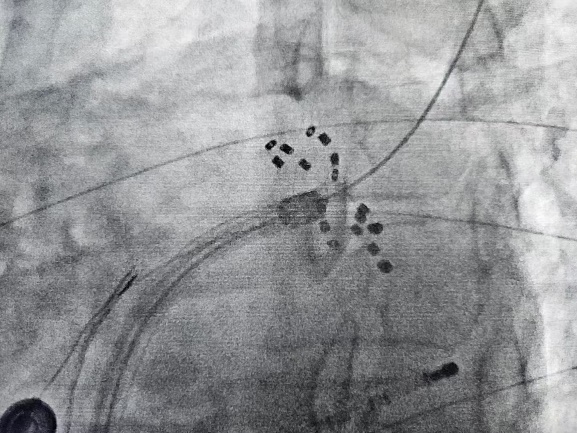

手术过程在三维导航系统辅助下精确实施,操作时间短,创伤小,患者术中舒适度高。FARAPULSE系统以非热能方式工作,避免了传统消融可能引起的心房食管瘘、膈神经损伤等并发症,同时确保高效消融效果。术后标测显示,患者肺静脉实现了完全电隔离,手术取得了圆满成功。

FARADRIVE导管以网篮和花瓣两种形态进行肺静脉消融